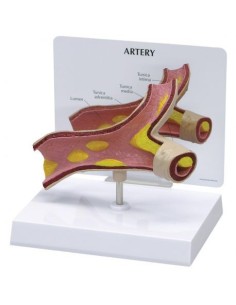

Dal cranio in 22 parti con incastri magnetici ai modelli di colonna vertebrale, da quelli di articolazioni a quelli di cuore, ogni pezzo della nostra collezione è progettato per un’immersione totale nello studio dell’anatomia umana. I nostri modelli, realizzati tramite scansioni di ossa vere, garantiscono un’esperienza tattile autentica e una fedeltà di peso quasi identica agli originali.

Essenziali per studenti e professionisti, i nostri modelli anatomici sono strumenti didattici che permettono di osservare le strutture anatomiche con precisione, eliminando la necessità di dissezioni o studi invasivi. Sono inoltre utili per spiegare ai pazienti le patologie, rendendo la comunicazione più efficace e risparmiando tempo prezioso.